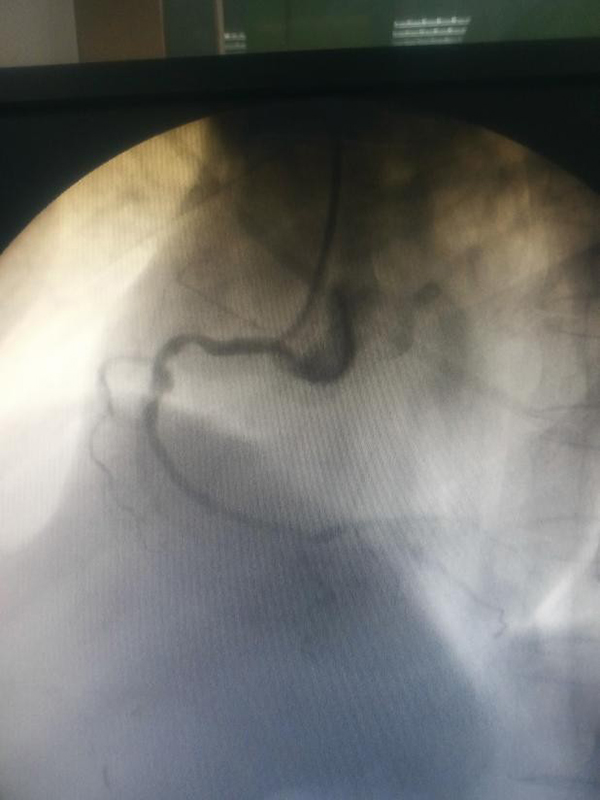

按照疫情防控要求,所有參與手術(shù)人員均做好全程防護(hù),嚴(yán)格執(zhí)行防護(hù)措施。這樣給手術(shù)帶來極大的不便。為了做好充分準(zhǔn)備,術(shù)前,徐通達(dá)主任早早將洗手衣、鉛衣、防護(hù)服、面罩、手術(shù)衣穿戴整齊。術(shù)中,徐通達(dá)主任克服了患者耳聾、不?人缘炔荒芎芎门浜弦蛩,以及由于防護(hù)需要防護(hù)鏡產(chǎn)生水汽不能清晰讀圖及造影圖片不清晰等多重困難因素,依靠多年來積累下的經(jīng)驗,沉著冷靜,嫻熟精準(zhǔn)操作,抽吸血栓,球囊擴張,迅速開通患者閉塞的右冠狀動脈,植入1枚支架,血流恢復(fù)至TIMI 3級,ST段回落,血壓上升,生命體征逐漸平穩(wěn)。經(jīng)過徐醫(yī)附院醫(yī)護(hù)團(tuán)隊的共同努力,患者得到成功救治。

術(shù)后,徐通達(dá)主任及其他術(shù)者脫掉密不透風(fēng)的防護(hù)服、沉重的鉛衣,手術(shù)衣、洗手衣早已浸滿汗水。但是看到患者轉(zhuǎn)危為安,在場所有人都如釋重負(fù);颊咝g(shù)后在市傳染病醫(yī)院ICU,經(jīng)程守全主任等醫(yī)護(hù)人員的精心治療護(hù)理下,生命體征平穩(wěn),恢復(fù)良好,并已順利轉(zhuǎn)至徐醫(yī)附院東院ICU繼續(xù)治療。